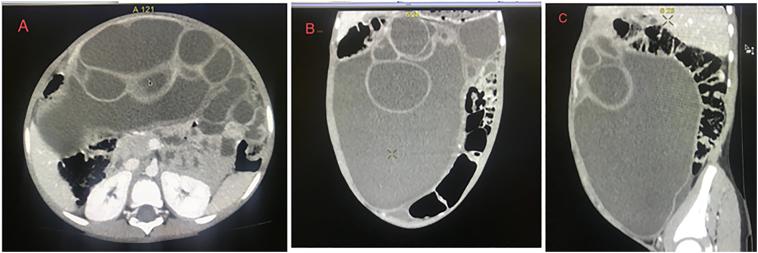

A 5-year-old boy was brought in by his parents to our hospital with abdominal swelling that had been persistent for a year, along with loss of appetite and weight loss. On examination, the abdomen was distended and dull on percussion. We considered mesenchymal hamartoma of the liver (MHL) as the top differential after an abdominal CT scan with contrast showed a multi-loculated cystic tumour. For both definitive diagnosis and therapy, the patient underwent exploratory laparotomy with excision of the cystic mass. Surprisingly, histopathology examination of the resected specimen revealed biliary mucinous cystadenoma (BCA).